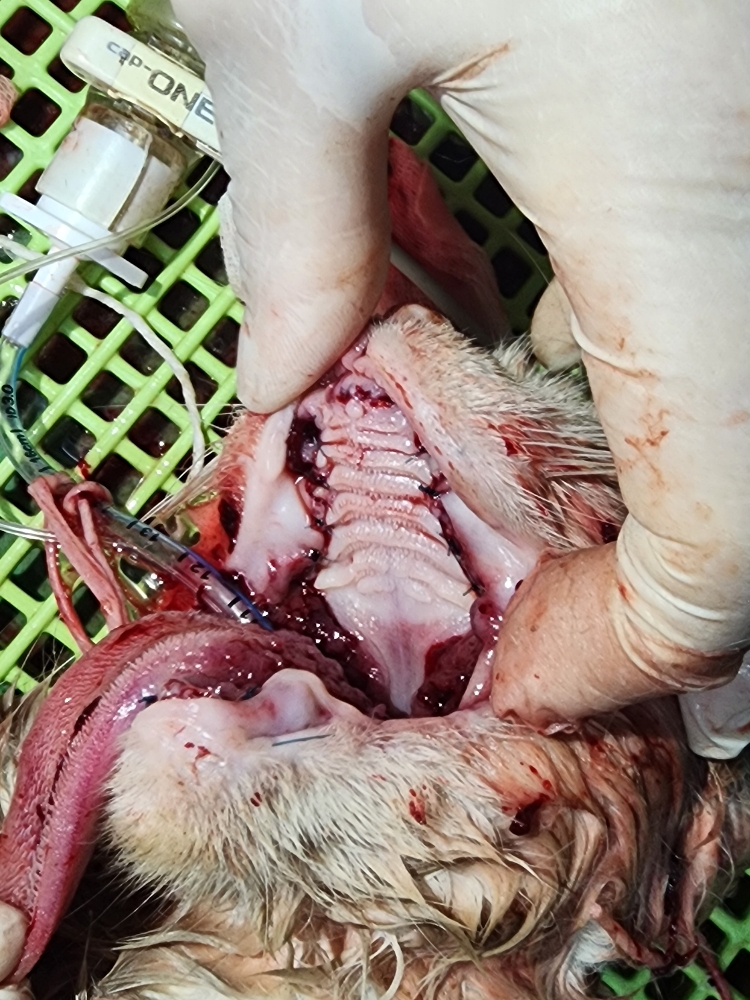

같이 구조한 소리아빠의 구조치료후 및 구조전 사진입니다.

| 대상묘신청당시상태 | 소리는 구내염이 심하여 침을 질질 흘렸고 고름도 흘리고, 눈에 염증도 있었습니다. 심한 탈수 상태로 건강이 급속히 악화되어갔습니다. 몇개월 동안 소리의 면역력 강화를 위해 꾸준히 영양제 및 항생제 급여로 케어해주었으나 상태가 점점 더 심해져만 갔고 잘먹지를 못했습니다. 소리는 중성화도 미실시된 상태였습니다. 새끼를 여러마리를 낳았으나 건강상태가 좋지 않아 제대로 수유를 하지 못해 한마리만 겨우 살아남아 수유중이었으나 어미모인 소리 상태가 좋지 않아 새끼와 같이 구조하였습니다. 같이 입원시켰으나 수유를 하지 않아 새끼는 인공수유 및 별도 케어중입니다. |

| 치료과정 | 올해 3월부터 하천 다리 밑에서 생활하던 치즈 가족인데 환경이 열악하여 돌보기 시작하여 조금씩 건강이 좋아지다 일주정도 사라졌다 다시나타났을때 상태가 좋지않아 이틀간 지켜보다 점점악화되어 가서 일가족을 8/14 저녁에 구조하여 15일 병원개원전 도착하여 1번으로 입원시켰습니다. 초기진료시 심한 구내염과 심한 탈수로 우선 수액부터 공급하시고 저녁쯤 전발치 수술을 하였어요. 중성화가 되어 있지 않아 수술을 같이 진행하였습니다. 한달전쯤 출산하여 새끼가 여러마리였으나 아빠냥, 엄마냥 모두가 심한 구내염과 치주염 그리고 탈수로 제대로 케어하지 못해 한아이만 살아있어 같이 구조했는데 소리 수술후 같은 케이지에 넣어주었으나 엄마가 수유를 거부하고 돌보지 않아 아기냥은 집으로 데리고가서 인공 수유를 시작하여 지금은 매우 건강하게 자라고 있습니다. 어미냥 소리는 몇일간 스스로 먹지를 않아 많이 걱정하였고 병원원장님과 간호사님들은 정성을 다해 수시로 돌봐주시고 케어해주셨어요. 수술후 2일간 전혀 먹지 않아 수액만 공급하다 3일째부터는 강급을 하였고 몇일후 자급을 하여 안심을 하게 되었습니다. 자급을 한 이후로 건강이 매우 호전되어 퇴원하였고 같이 구조하여 수술 및 치료 입원한 소리아빠와 같이 퇴원하여 집의 욕실과 욕실 전실을 구획하여 격리케어중으로 건강을 차츰 회복하고 있습니다. 중간에 수술부위를 확인차 병원에 들렸는데 수술부위가 덜 아물어 추가 투약을 하고 있고 이번주 투약이 끝났습니다. |

같이 구조한 소리아빠의 구조치료후 및 구조전 사진입니다.

치료중사진입니다.

우선 치료전 사진입니다.